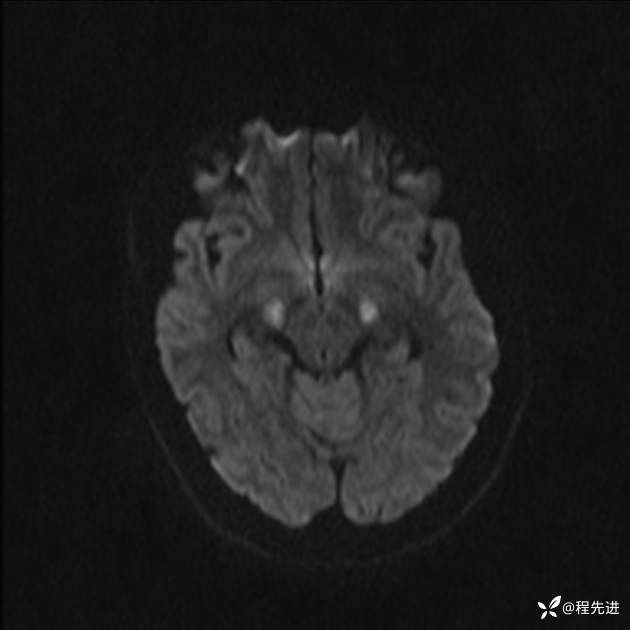

【患者信息】:女,25岁

【现病史及既往史】:言语含糊、意识状态改变1天。有下段剖宫产术10天病史。